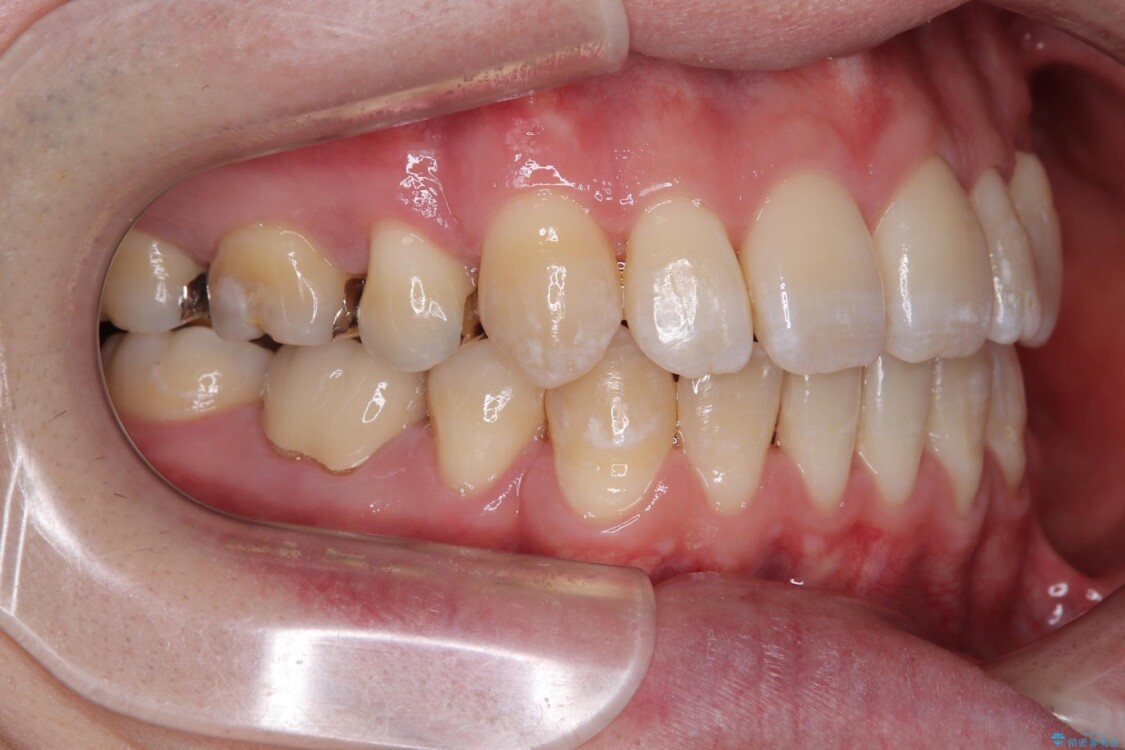

治療前

• 口元の突出感を改善!目立ちにくいワイヤー矯正で自信を持てる自然な横顔に 治療前画像

「横から見ると唇が前に出て見えるのが気になる…」 「マスクを外すのが恥ずかしい…」 そんな口元の突出感に悩まれてご来院された患者様。

精密検査の結果、上下左右の小臼歯4本を抜歯し、そのスペースに前歯を後方へ移動させる矯正治療をご提案しました。

装置は、透明感のあるクリアブラケットとホワイトコーティングされたワイヤーを使用した、目立ちにくい審美装置を選択。